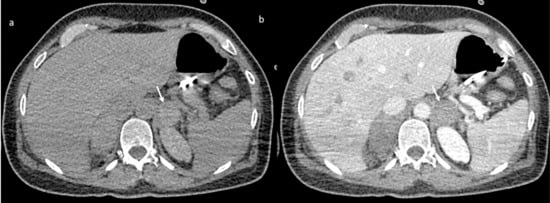

A brain computed tomography (CT) scan showed multiple subacute intra-axial hemorrhages in atypical locations, including the right frontal and the temporal lobes (Figure 1), with ipsilateral hemorrhagic subarachnoid suffusion, raising the suspicion of Labbè/superior longitudinal sinus thrombosis, even if brain angio-CT demonstrated only a non-occlusive thrombosis of the vein of Galen (Figure 2a), but also a floating thrombus within the aortic arch (Figure 2b).

Figure 1.

Brain computed tomography (CT) scan: presence of multiple subacute intra-axial hemorrhages in atypical locations (a,b).